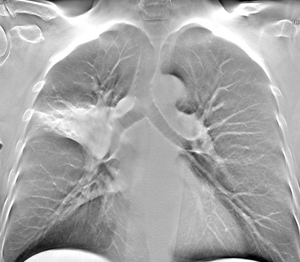

Болюсное контрастирование: Визуализация легких